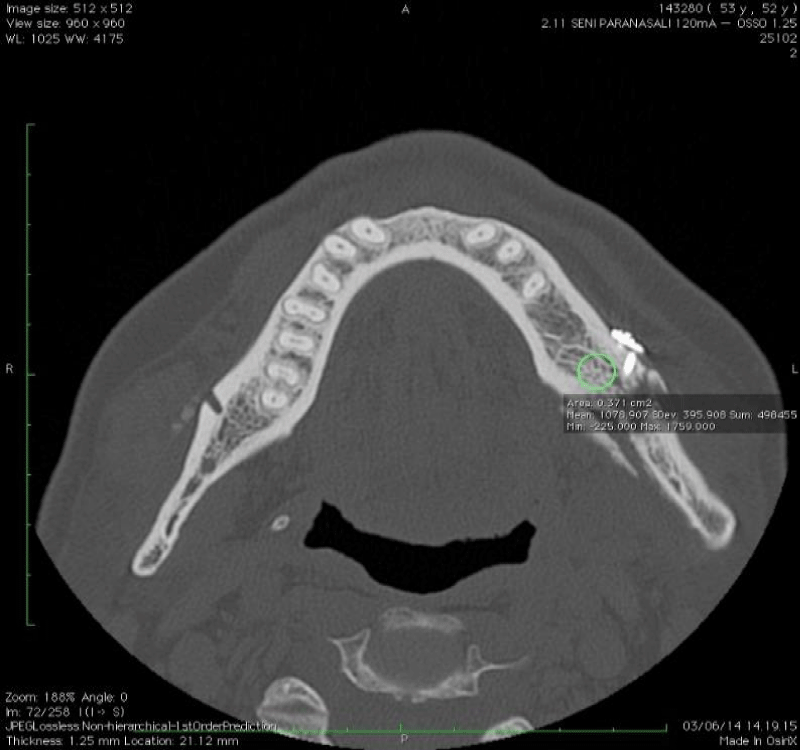

Figure 7:

Axial CT image showing ROI placement for bone density measurement.